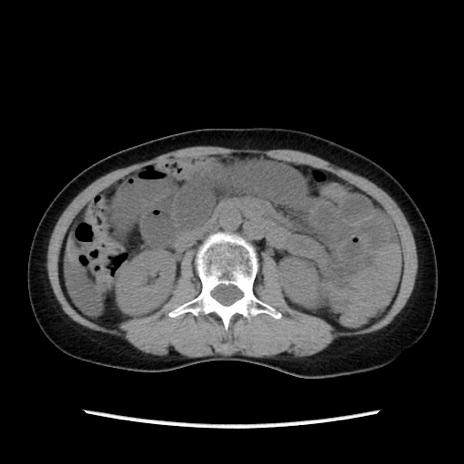

症例32(横断像)

【症例】40歳代 女性

【主訴】上腹部痛、嘔気・嘔吐

【現病歴】約9時間前頃から急に上腹部痛、嘔気、嘔吐が出現。改善しないため救急要請。

【既往歴】子宮頚癌(広汎子宮全摘術、放射線療法)、腸閉塞

【身体所見】腹部:平坦、軟、腸雑音亢進、上腹部を中心に腹部全体に圧痛あり。

【データ】WBC 8400、CRP 0.03